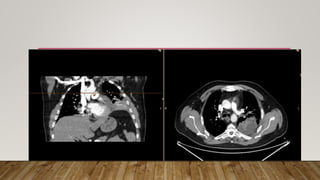

22/10/2023 CT CHEST AND ABDOMEN

22/10/2023 CT AORTA

• On (22/10) CT was performed for this pain showing Lt sided retroperitoneal

hematoma